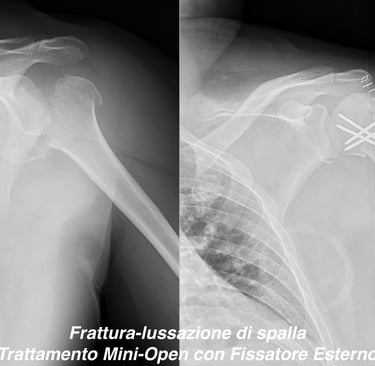

Patologia traumatica di spalla (scapola, clavicola e omero)

Gallery

Attività Chirurgica